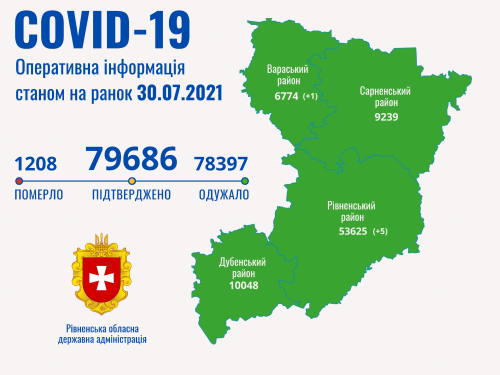

Коронавірус повертається: як стрімко зростає кількість хворих на Рівненщині (ВІДЕО)

Пів тисячі - у важкому стані, 9 жителів Рівненщини померли за добу від коронавірусу